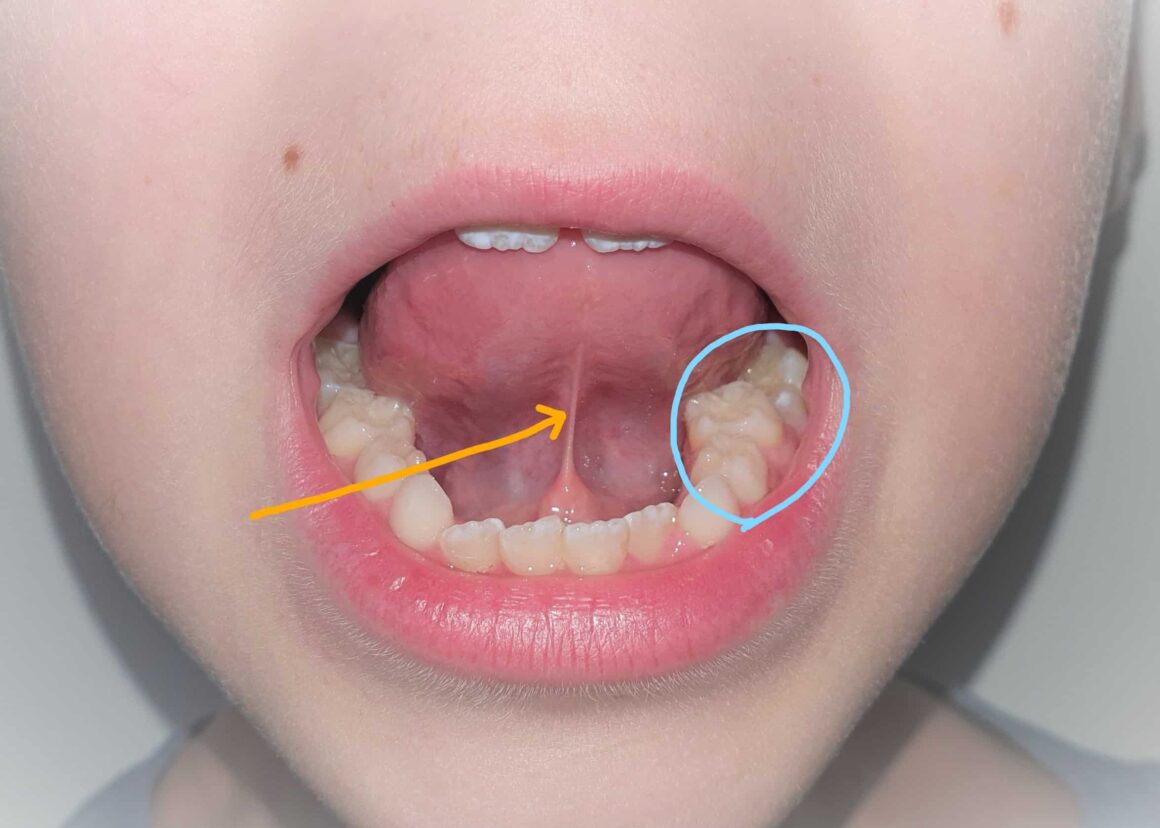

Step By Step Guide To Checking For Tongue & Lip Ties Can Ent Diagnose Tongue Tie interest in the treatment of ankyloglossia (tongue tie) has continued to grow since enttoday first reported on diagnosis and treatment in 2019, and disputes. pediatric otolaryngologist jonathan walsh and colleagues recently established boundaries for the definition, diagnosis and treatment. most cases of tongue tie are treated as soon as they are diagnosed, and depending on the child’s. Can Ent Diagnose Tongue Tie.

Lip and Tongue Ties How to check for one, Revision Tips, and Post Can Ent Diagnose Tongue Tie most cases of tongue tie are treated as soon as they are diagnosed, and depending on the child’s age, it can be done either in the. interest in the treatment of ankyloglossia (tongue tie) has continued to grow since enttoday first reported on diagnosis and treatment in 2019, and disputes. what you need to know. pediatric. Can Ent Diagnose Tongue Tie.